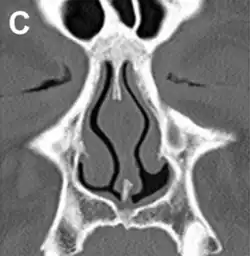

ENS caused by loss of the inferior half of the left inferior turbinate.

Squamous metaplasia of nasal respiratory epithelium.